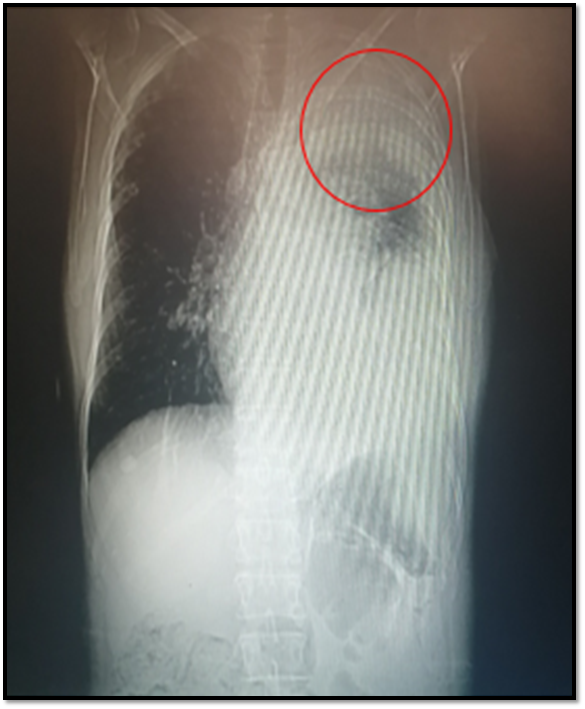

If we have the clinical suspicion that the patient has a probable Pancoast tumor because it has specific symptoms (shoulder pain and Horner's Syndrome) we must perform a first line image study, in this case the simple chest X-ray is of great help in lateral and posterior-anterior projections, where we could observe the lesion occupying space (mass) at the level of the affected pulmonary vertex.

From the outset, a chest radiography is requested, where there is evidence of left pleural effusion that takes the base and third, where the opacity of approximately 5x5cm in the upper ipsilateral vertex draws attention. A sample of this pleural fluid (cytological, cytochemical and culture) is taken, this being negative. Simple chest tomography is performed where the following is observed:

@anaestrada12

Space-occupying lesion with mass effect at left pulmonary vertex level of approximately 5x 7,2cm. Accompanied by septate ipsilateral effusion.

Suggestive images of bone metastasis at t5, t4 and sternum levels are also observed.